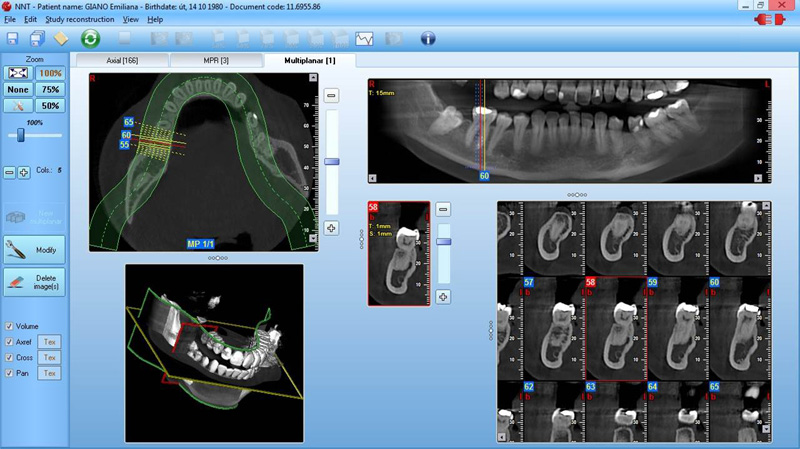

NewTom Implant Planing

Jedná se o plánovací program, který využívá dat získaných při vyšetření pomocí přístroje New Tom. Tento program umožňuje tříprostorovou počítačovou simulaci při plánování pozic implantátů.

Součástí programu je i databáze, ve které mohou být uloženy všechny typy implantátů od všech výrobců, včetně jejich délek, průměrů i tvarů.

Lékař si vytvoří všechny typy zobrazení potřebných pro naplánování – tedy 2D snímky (panoramatický), příčné řezy i 3D model.

Vidí zde i důležité anatomické útvary – čelistní dutinu, průběh nervu atd. Po proměření množství kosti – šířky i výšky vybere z databáze vhodný typ implantátu a umístí ho do požadované lokality.

Ihned vidí jeho pozici ve všech 3 rovinách a na všech snímcích i 3D modelu. Může upravovat podle potřeby jeho pozici, sklon atd.

Všechny vybrané a správně umístěné simulované implantáty se ukládají do „počítačové karty“ pacienta s jejich pozicí, délkou, průměrem, typem i sklonem.

Lékař i pacient tedy ještě před vlastní operací vidí, jak by mělo ošetření probíhat a vypadat.